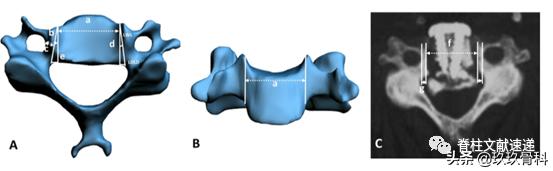

文中通过影像学测量出如下数据

文章认为钩突尖可以作为开槽的解剖标志,开槽后距离横突孔约2mm距离。下图为尸体解剖图片,a开槽线位于钩突尖内侧,b横突孔内缘,c椎弓根内缘投影,神经钩紧贴椎弓根。

从解剖来说,ACAF不易损伤椎动脉,但考虑到解剖变异,术前行CTA检查是有帮助的。作者提出3条避免损伤椎动脉的技巧。1)避免使用粗钻头截骨开槽,2)术中保持中线,参照钩突尖部,3)术中随时探查截骨外壁的完整性,这一步尤其重要。